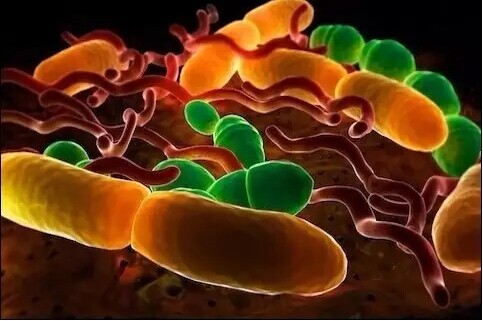

细胞

尘螨